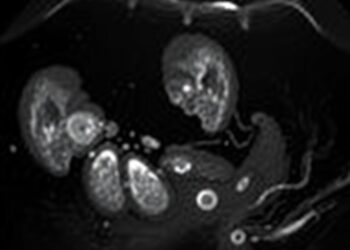

Measuring Endometrial Thickness: Essential for Ovarian Cyst Diagnosis